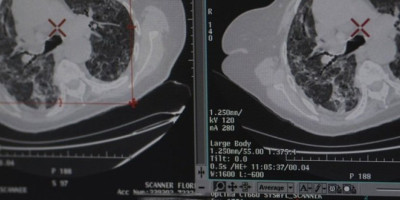

Međutim, lekari su bili zbunjeni kada su rezultati testa 41-godišnjaka na dijabetes bili negativni. Umesto toga, uzrok ekstremne žeđi poštara bio je tumor na mozgu koji se nalazi u njegovoj hipofizi.

Deo mozga veličine graška pomaže u regulisanju osećaja žeđi, singalizirajući nam da pijemo vodu kada otkrije da smo dehidrirani, alio u slučaju Plamera, sistem "se pokvario" i nalagao mu je da pije oko pet puta više od preporučene količine svakog dana.

Plamer, iz Falmuta u Kornvolu, morao je da prođe 30 krugova radioterapije, ali sada nema tumora.

- Osećao sam stalnu žeđ koju nisam mogao da utolim i došao sam do tačke kada sam izbacivao onoliko vode koliko sam pio. Bilo je to užasno vreme, nisam mogao da idem na posao, osećao sam ekstremni umor.

Rekao je da je bio "razoren" kada su mu saopštili dijagnozu. Dobio je steroidnu terapiju kao deo lečenja raka, što je imalo neželjeni efekat jer se ekstremno ugojio. Zbog tretmana nije mogao da igra ragbi i kriket, nešto što je ranije obožavao.

- Uvek sam bio veoma aktivan i igrao sam ragbi i kriket nedeljno, što je nešto čemu nikada nisam uspeo da se vratim. Počeo sam da trčanje i plivanje i uspeo da povratim kontrolu nad svojom težinom - kaže Plamer koji sada sakuplja novac za dobrotvornu organizaciju koja se bavi izičavanjem tumora mozga.